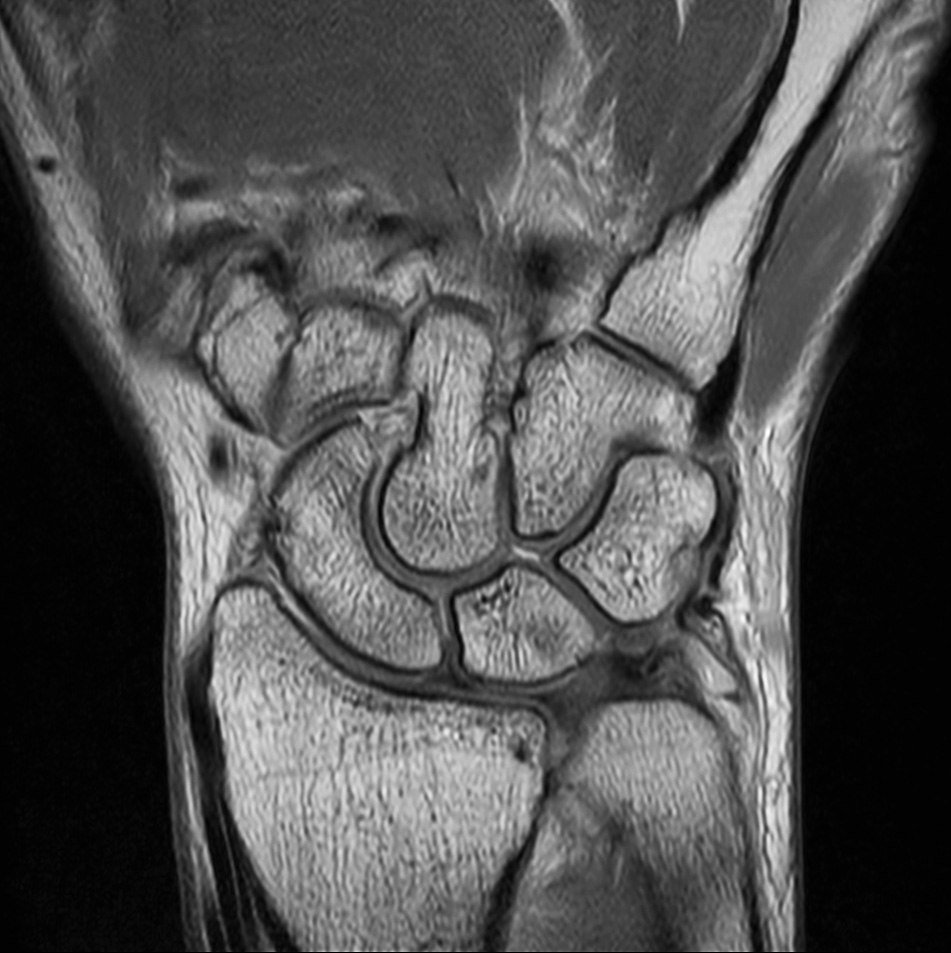

Comprehensive wrist imaging